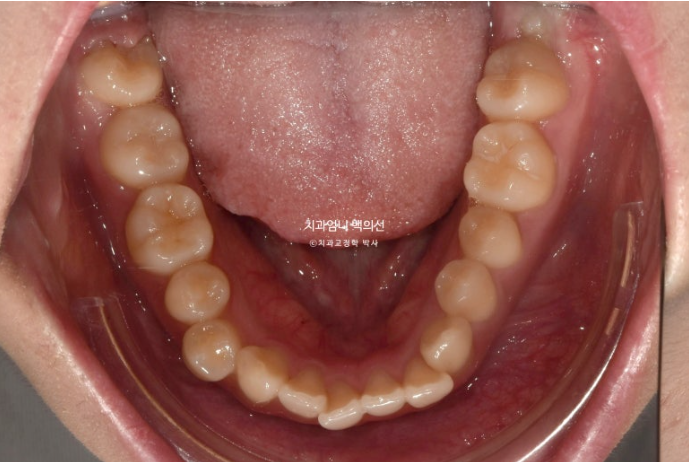

앞니가 뻗쳐 있습니다.

다행인건 가용한 사랑니 공간이 충분한 점입니다.

즉 작은어금니 발치 없이 사랑니 공간을 이용하여 교합을 맞추고 중심선을 맞추기로 했습니다.

비발치로 덧니를 펴면 생기는 문제점은 앞니가 앞으로 돌출된다는 것인데 이 부분도 어금니를 사랑니공간으로

밀어 해결하기로 했습니다.

또한 뻗친 앞니 각도도 개선해야합니다.

인비절라인 치료 선택하셨고 사랑니 발치 후에 치료도 진행했습니다.